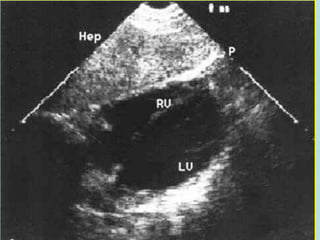

• Investigations : FAST , DPL , CT , Angiogram

Diagnosis

3. Investigations

* pelvic film : AP , Inlet , Outlet , Judet

* FAST

* DPL

* CT scan

* Angiography